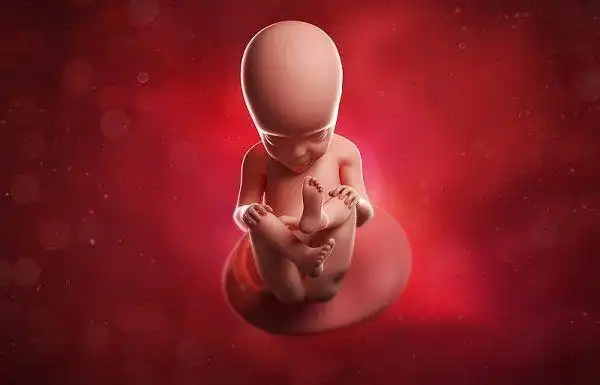

怀孕18周胎儿真实图

怀孕18周胎儿发育图

by lennart nilsson, 1965年 fetus, weeks(十八周的胎儿)

18周胎儿在母体内的真实图片长什么样

18周的胎儿